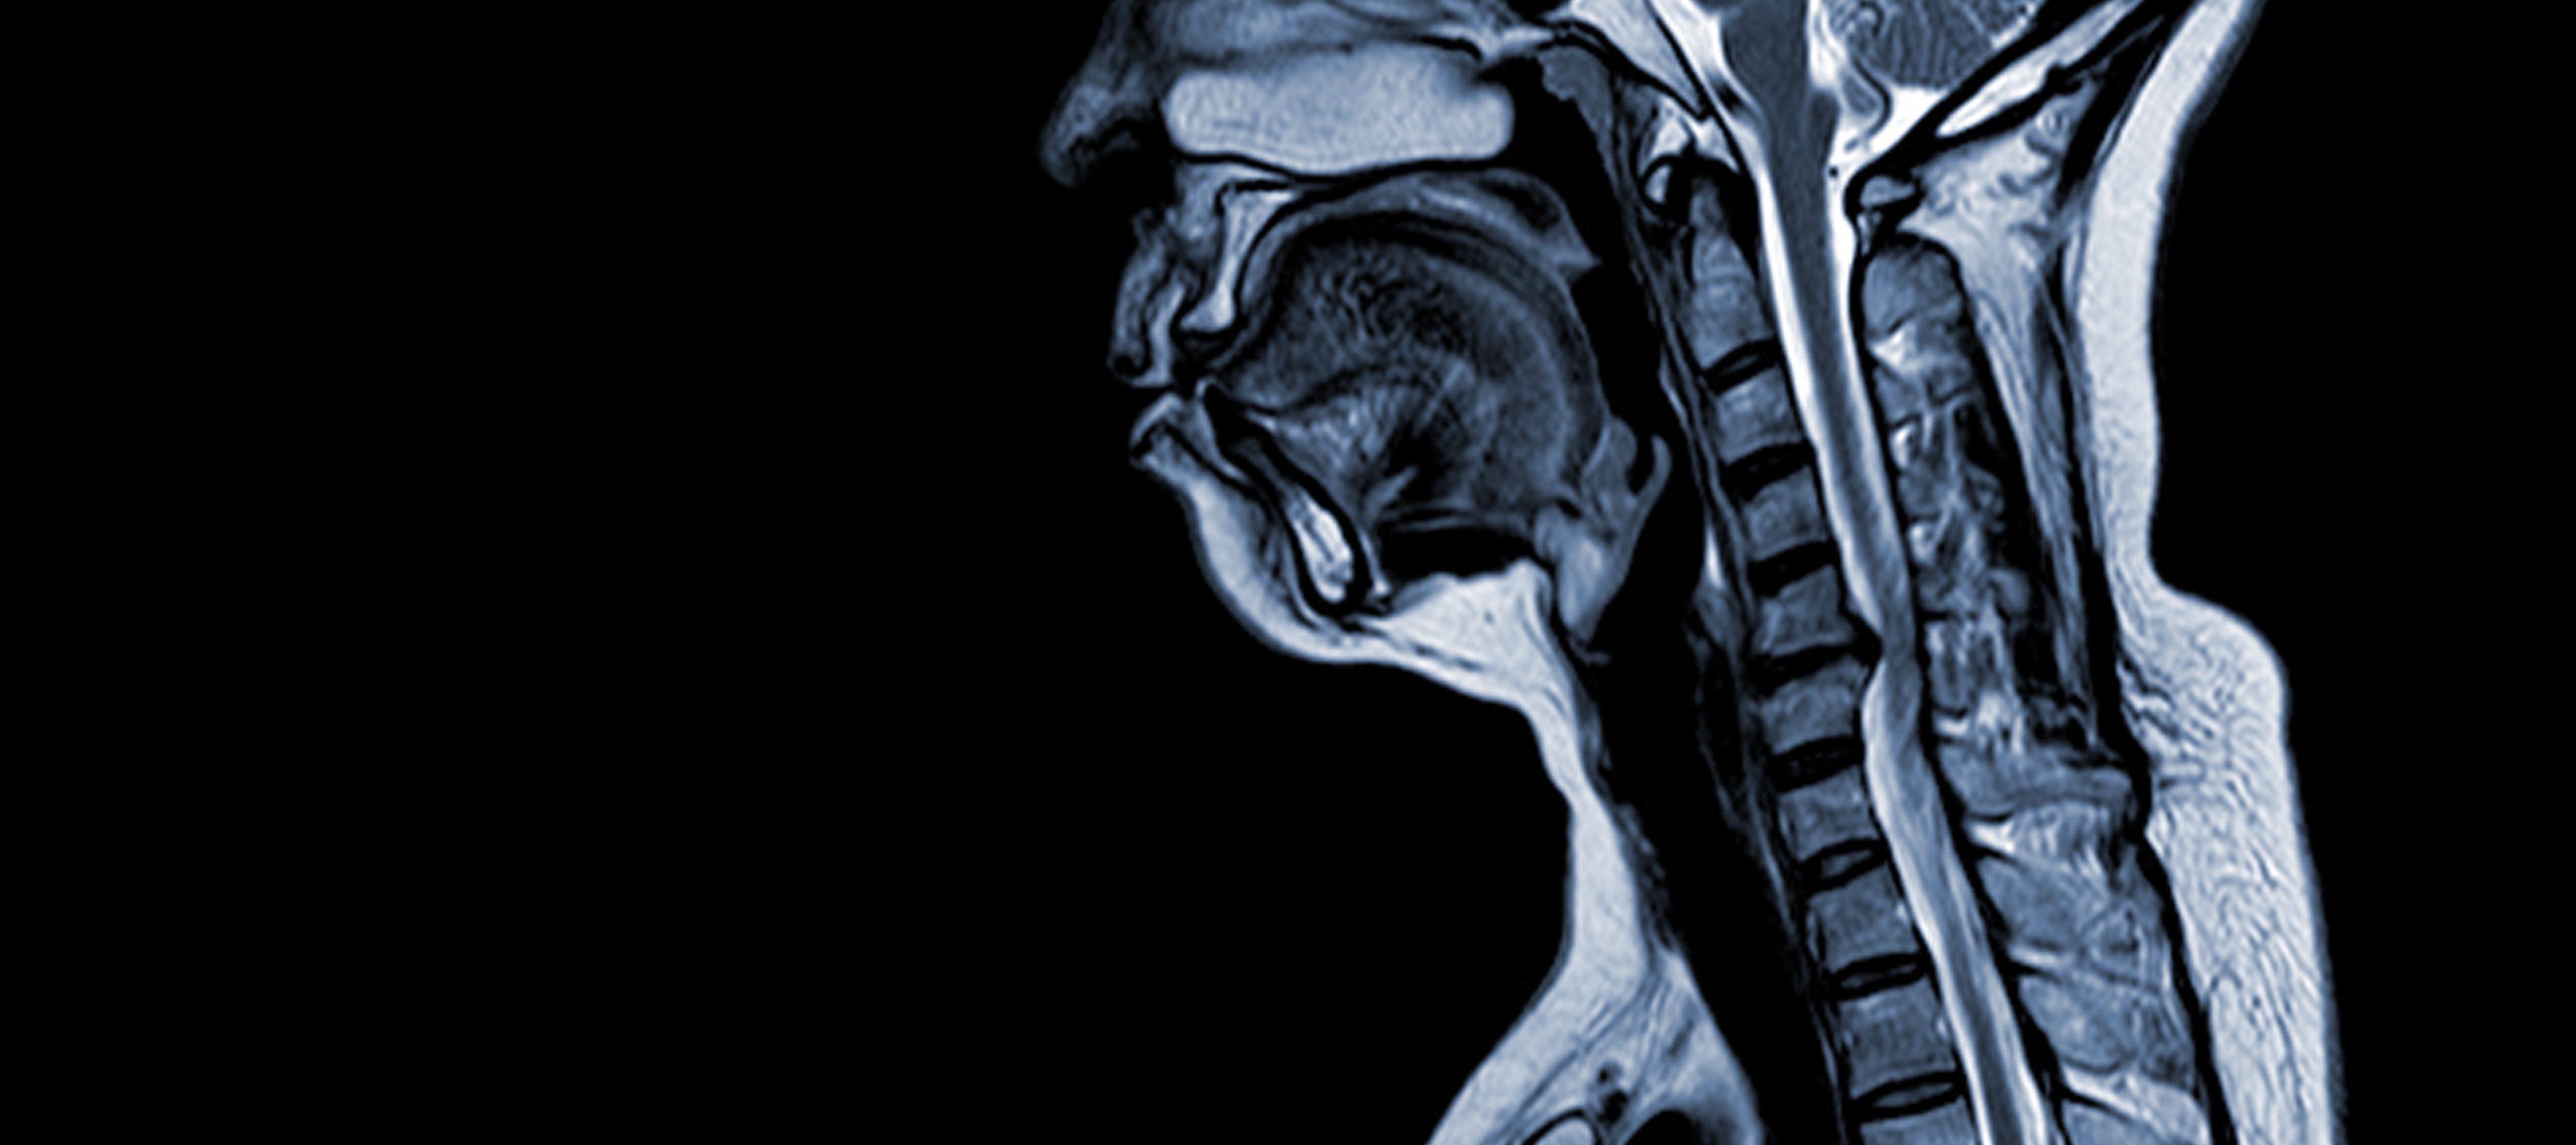

Цервикалната спондилотична миелопатия (CSM) е неврологично заболяване, което е водещата причина за увреждане на гръбначния мозък при възрастни. Накратко казано, става дума за притискане или увреждане на гръбначния мозък в областта на шията, главно поради естествения процес на стареене, който засяга шийните прешлени. Терминът "миелопатия" произлиза от гръцките думи "myelon", което означава "гръбначен мозък", и "pathos", което означава "болест".

CSM е сложно заболяване с многофакторна патофизиология, която включва структурни промени в шийния отдел на гръбначния стълб. Няколко ключови фактора допринасят за развитието и прогресирането му:

- Дегенерация на диска (изпъкнал диск): CSM често започва с дегенерация на междупрешленните дискове в шийния отдел на гръбначния стълб, което води до тяхното издуване или изпъкване в гръбначния канал.

- Субпериостална костна формация (вентрално от гръбначния канал): В отговор на повишеното механично натоварване организмът образува нова костна тъкан от предната (вентрална) страна на гръбначния канал, което може да стесни пространството за гръбначния мозък.

- Осификация на задната надлъжна връзка: Задният надлъжен лигамент може да претърпи вкостяване, втвърдяване и калциране, което допринася за стесняването на гръбначния канал.

- Хипертрофия на Ligamentum Flavum: Хипертрофията на Ligamentum Flavum води до неговото удебеляване и намаляване на гъвкавостта му, което води до допълнително навлизане в пространството на гръбначния канал и притискане на гръбначния мозък.

Тези структурни промени заедно водят до компресия и стесняване на гръбначния канал, което води до характерните симптоми и усложнения, свързани с ХСМ. Разпознаването на тези рискови фактори и разбирането на свързаните с тях патофизиологични механизми е от съществено значение както за превенцията, така и за лечението. Ранното диагностициране и подходящите интервенции са от решаващо значение за смекчаване на последиците от тези структурни промени върху гръбначния мозък.